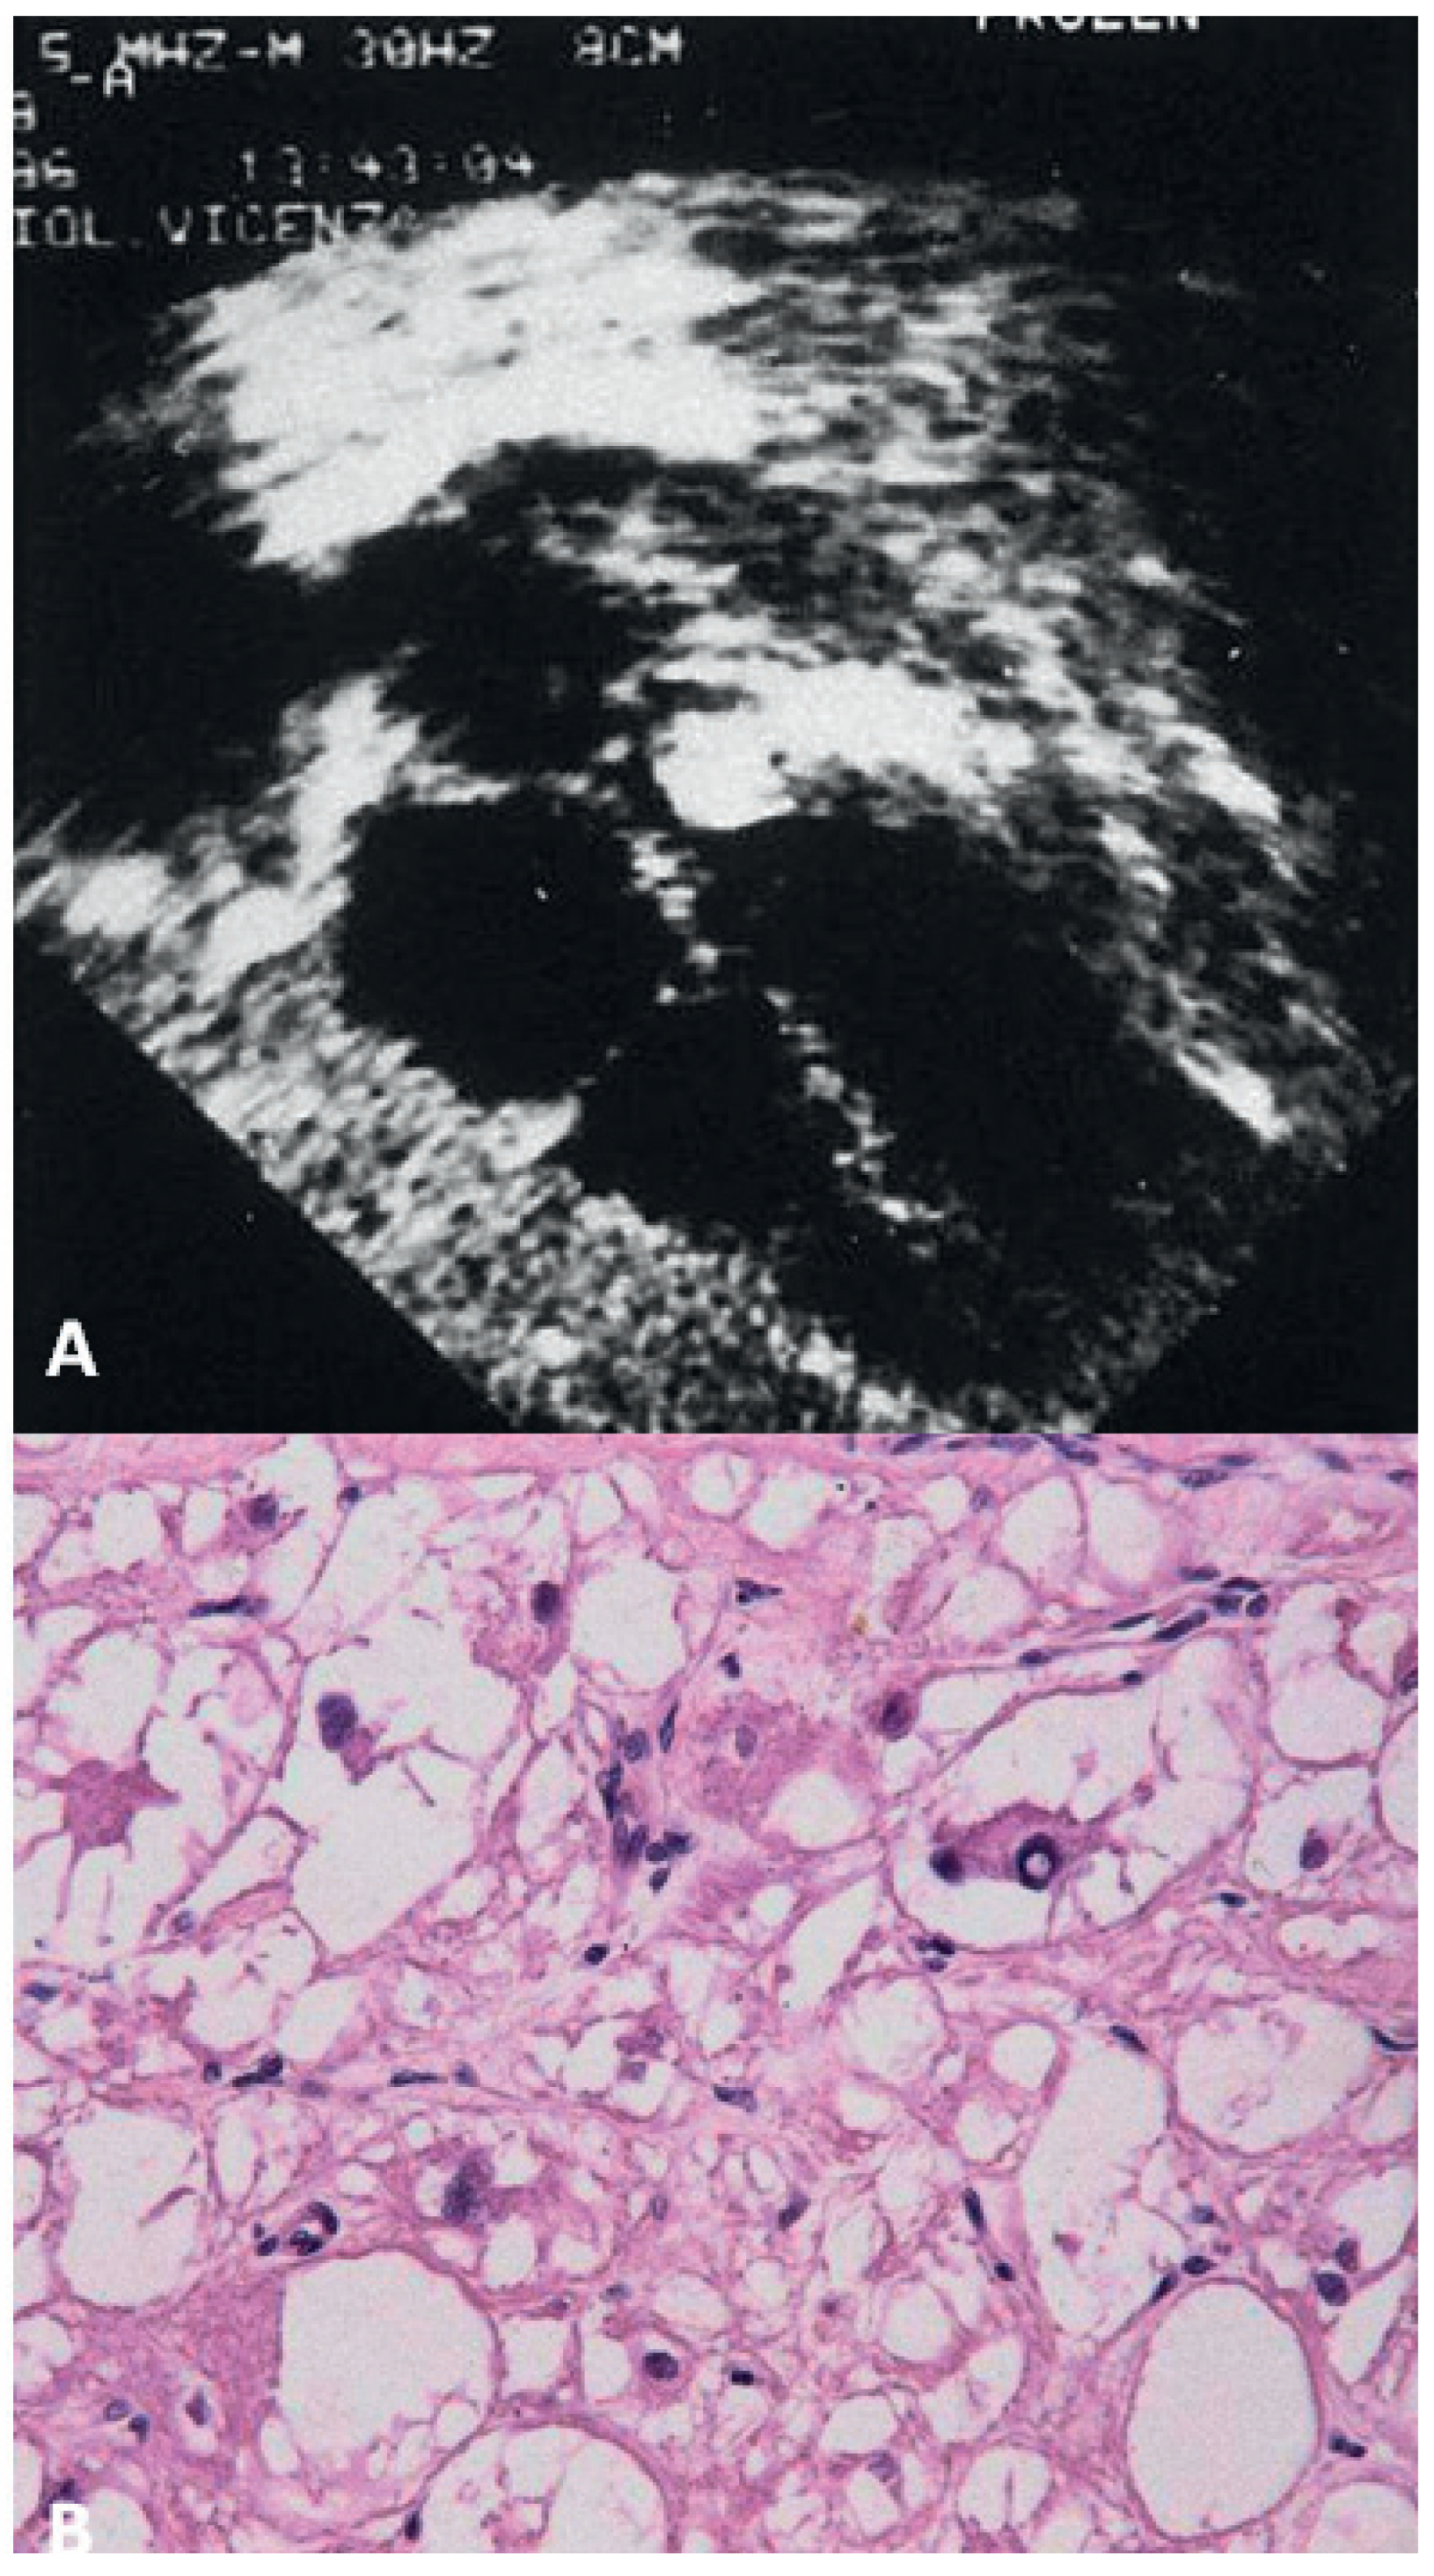

Myxoma

- Valente, M. Structural profile of cardiac myxoma. Appl Pathol. 1983, 1, 251–263. [Google Scholar]

- Padalino, M.A.; Basso, C.; Moreolo, G.S.; Thiene, G.; Stellin, G. Left atrial myxoma in a child: case report and review of the literature. Cardiovasc Pathol. 3002, 12, 233–236. [Google Scholar] [CrossRef]